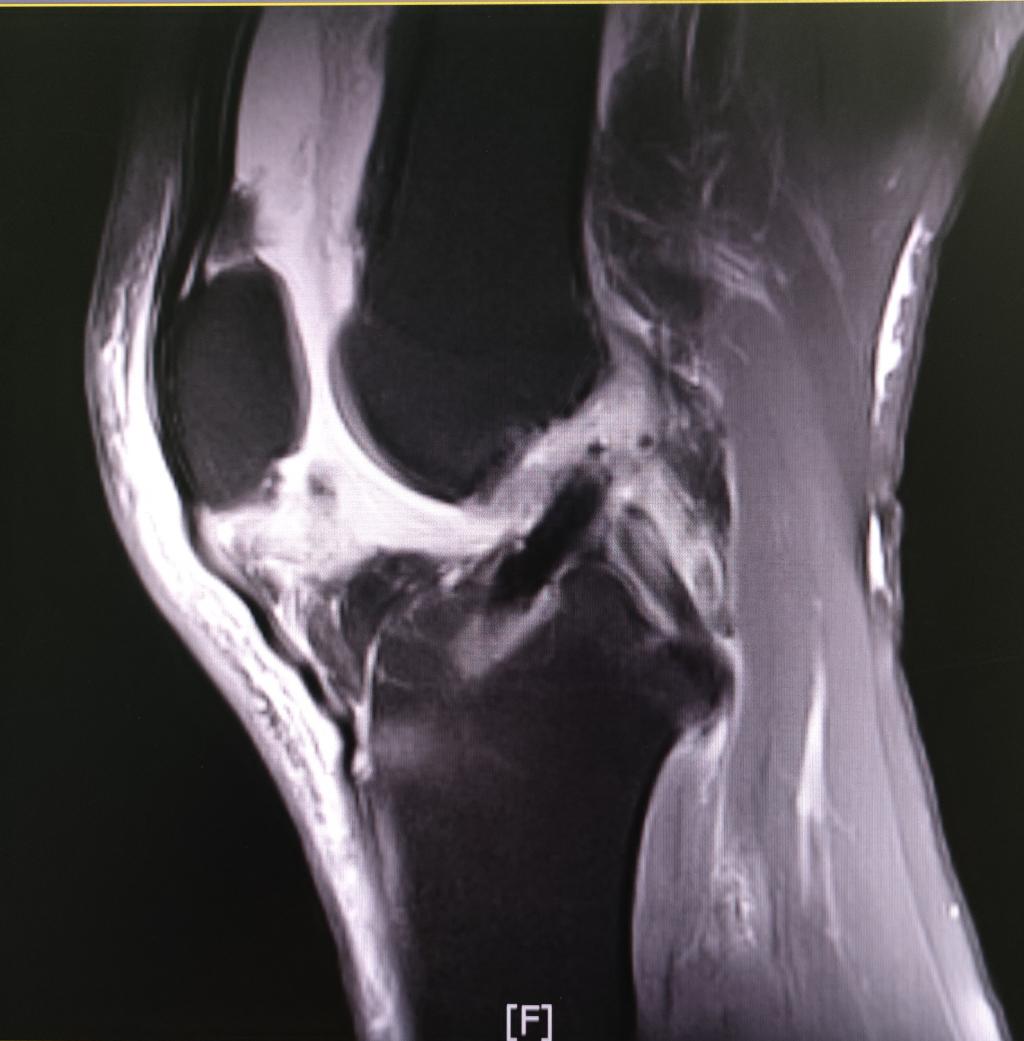

术后复查核磁